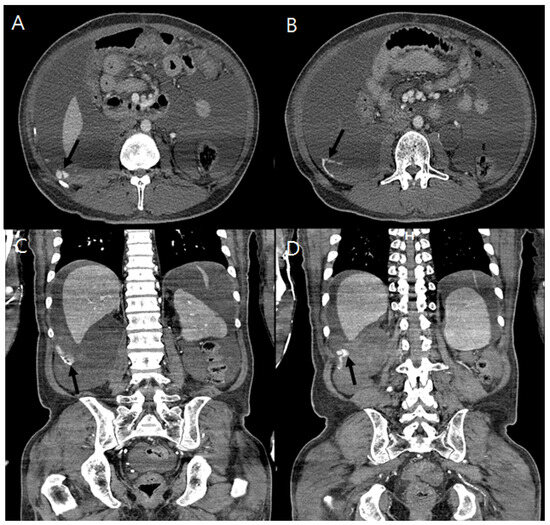

The spontaneous rupture of a subcostal (12th intercostal) artery is exceptionally rare and could be fatal, requiring early diagnosis and treatment. Only one case of intercostal artery (ICA) bleeding in a patient undergoing hemodialysis (HD) has been reported. We additionally describe a 41-year-old [...] Read more.

The spontaneous rupture of a subcostal (12th intercostal) artery is exceptionally rare and could be fatal, requiring early diagnosis and treatment. Only one case of intercostal artery (ICA) bleeding in a patient undergoing hemodialysis (HD) has been reported. We additionally describe a 41-year-old man undergoing HD who presented with a spontaneous hemoperitoneum and shock resulting from a subcostal artery rupture. He initially complained of diffuse abdominal pain and dizziness at the emergency room. His abdomen was bloated, and there was tenderness in the right upper quadrant area. Enhanced computed tomography and arteriography revealed a rupture of the right subcostal artery. After the super-selection of the bleeding artery by a microcatheter, embolization was performed using a detachable coil and gelfoam. In a subsequent arteriogram, additional contrast leakage was no longer detected, and his blood pressure was restored to normal. The patient was discharged without any sequelae. He was followed up at our HD center without recurrence of ICA bleeding. To the best of our knowledge, this is the second case in the English literature documenting a spontaneous ICA rupture in a patient undergoing HD. This case indicates that injury to ICA should be suspected when patients undergoing HD complain of abdominal or chest pain and dizziness, although it is very rare. Full article